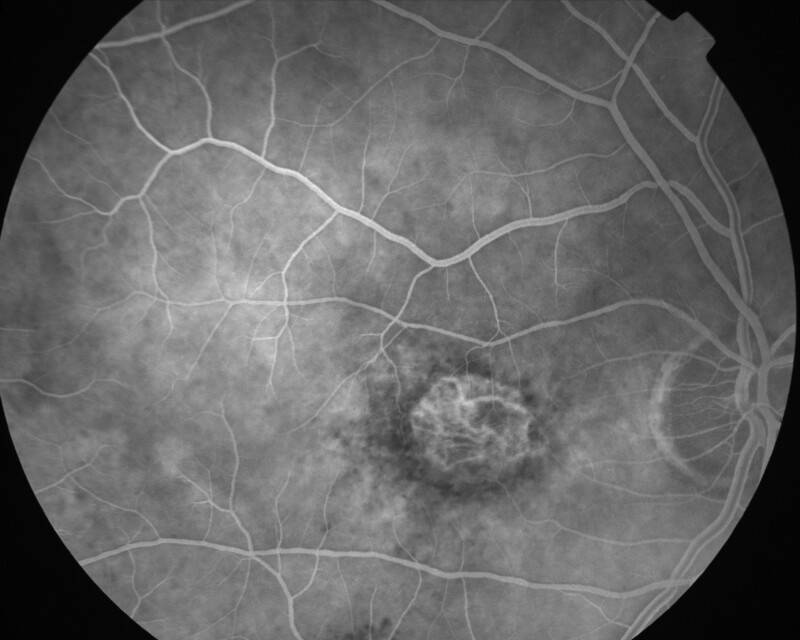

ATROPHIE AREOLAIRE CENTRALE

IMG0002.JPG